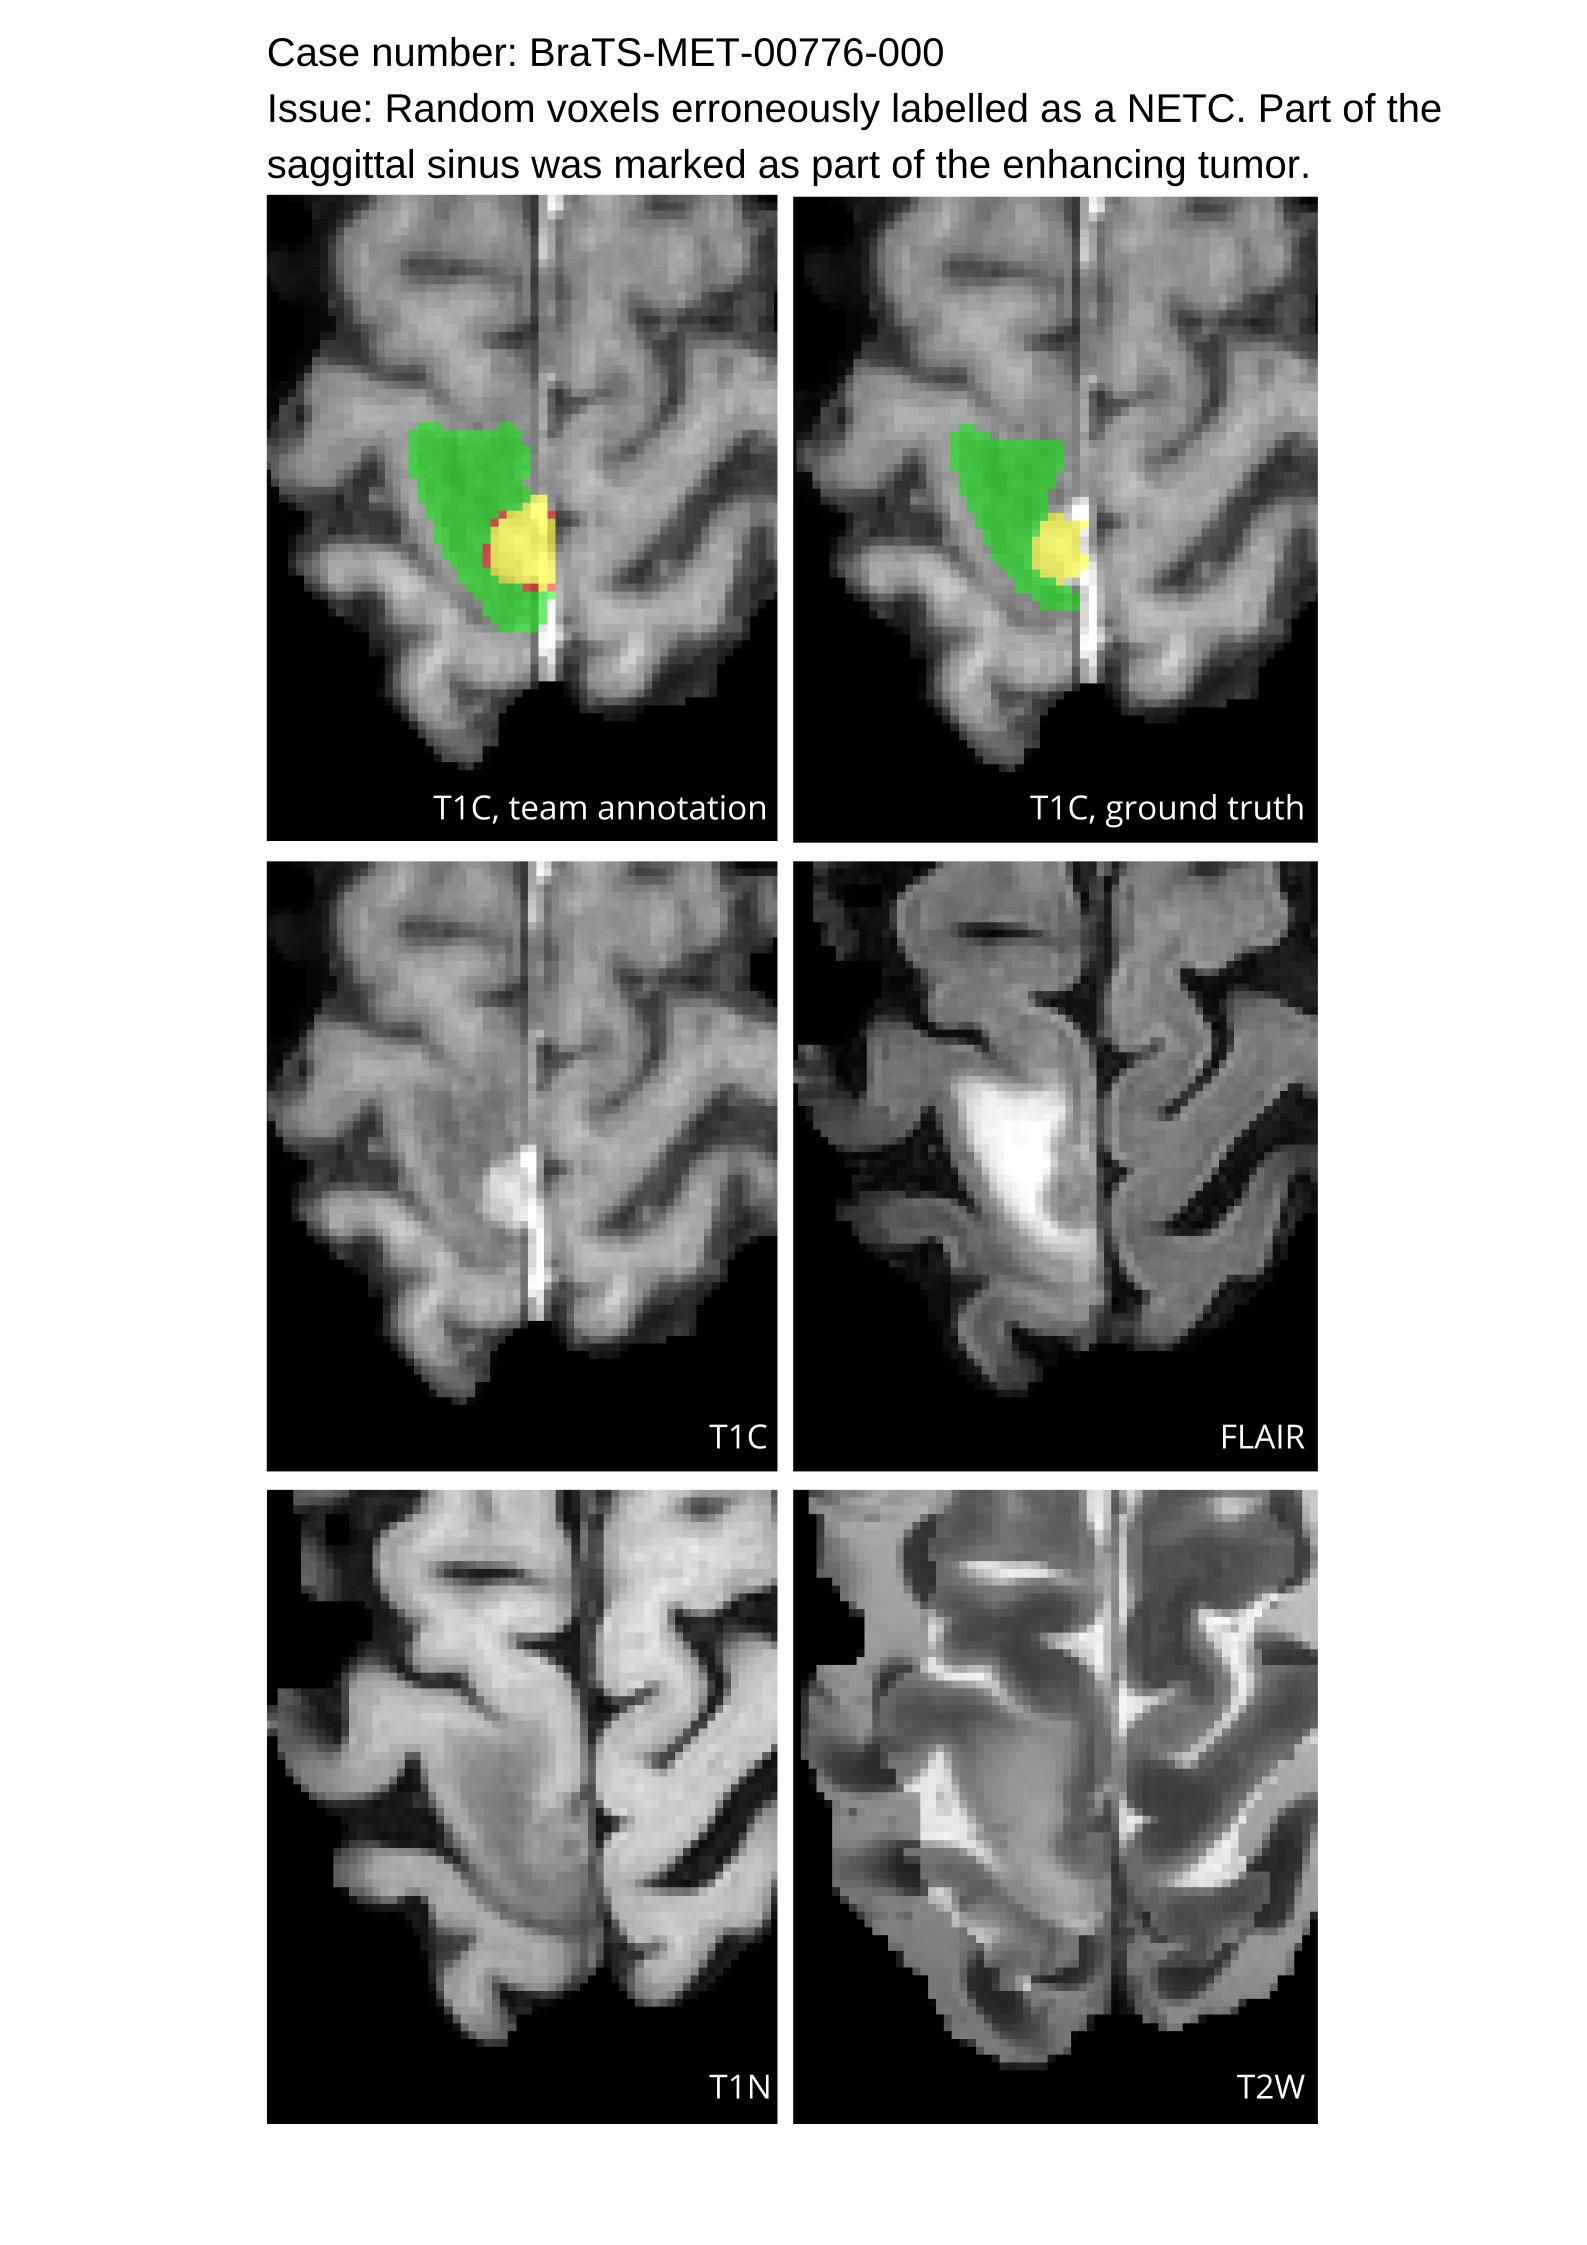

Approvers reviewed the volunteer annotations and either approved the case or returned it to students for re-annotation. Additionally, a QC process was implemented, which included removing all random voxels and any voxels outside the brain mask, ensuring all images had the same parameters (space, orientation, and origin) as the SRI24 atlas, and verifying the presence of all segmentations and segmentation masks are in the folder with original NIfTI images.